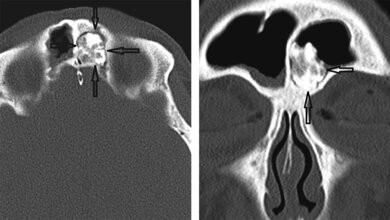

Anomalien und Normvarianten – Interne Veränderungen 2.18: Maldescensus testis

Schlüsselwörter: Maldescensus testis, Röntgen, Sonografie, CT, MRT

Keywords: Maldescensus testis, X-ray, ultrasound, CT, MRI